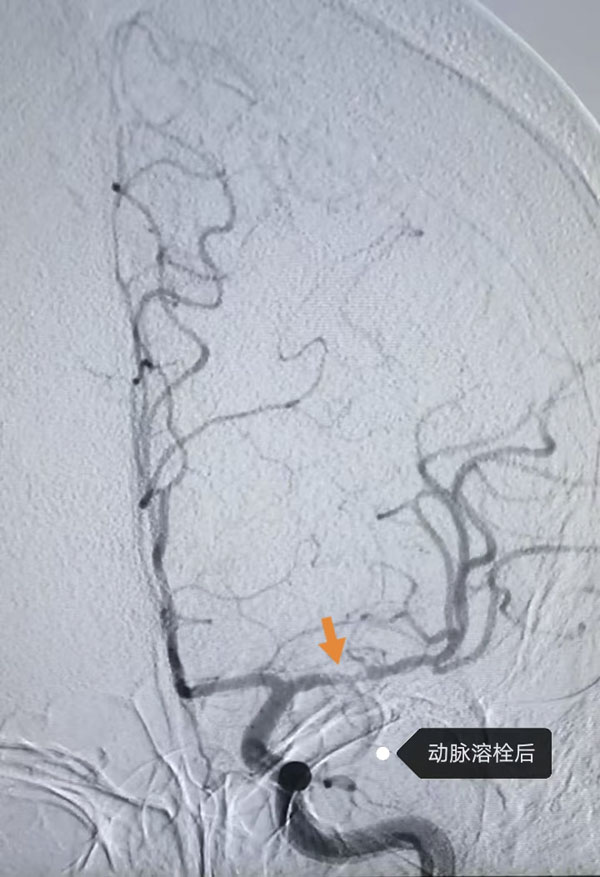

鑒于患者病情危急,接診醫生李晨曦緊急聯系介入組李彥青醫生啟動卒中救治流程,在介入手術室的人員的幫助下,為其實施腦動脈造影術。術中,李彥青發現患者此次發病的責任血管“左側大腦中動脈”雖存在血流再通,但局部仍為重度狹窄且血栓負荷重,遂決定通過左側頸內動脈給藥以改善局部血供。給藥后,復查造影顯示狹窄程度明顯改善。術后,患者NIHSS評分(神經功能缺損評分)由入院時的8分快速降至3分,言語及右側肢體活動不利明顯改善。一周后出院時,評分進一步降至1分,言語及肢體活動基本恢復正常。